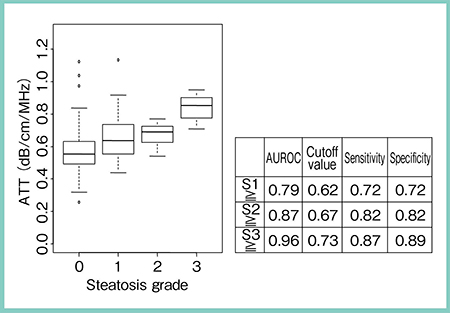

通常,エコービームは深部ほど減衰が大きくなることから,日立はSWMと連動して超音波減衰(ATT)を計測する機能を開発し,ARIETTA 850に搭載した。われわれは,ATTを用いて慢性肝疾患353名の減衰と脂肪化の程度の相関を検討した。まず,各症例の病理組織の脂肪化面積を自動算出して定量し,病理学的な脂肪化の程度(steatosis grade)と比較したところ,明らかな正の相関が見られた。また,ATTとsteatosis gradeとの比較でも同様であり(図4),ATTを測定することで肝の脂肪化の程度を非侵襲的に予測可能であった。一方,ATTと,線維化ステージおよび炎症を比較すると,いずれもATTにはまったく変化が見られなかった(図5)。ATTは純粋に脂肪化の程度を反映して定量化できることから,今後,ATTの測定は臨床でも普及すると考えられる。

図4 ATTとsteatosis gradeとの比較6)